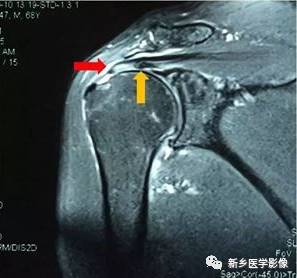

病例十:

冈上肌腱分层撕裂

红色箭头:关节面肩袖

黄色箭头:滑囊层肩袖